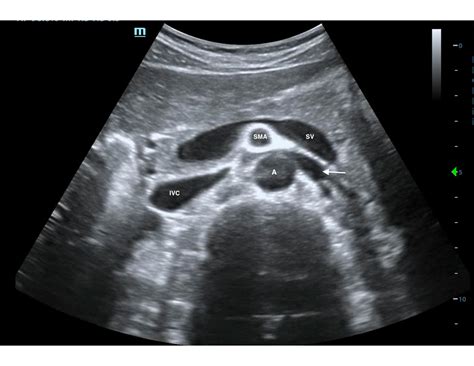

• Abdominal Aorta: Checking for aneurysms or other abnormalities in the abdominal aorta.

• Abdominal Aortic Aneurysm: The presence and size of an aneurysm in the abdominal aorta can be assessed.